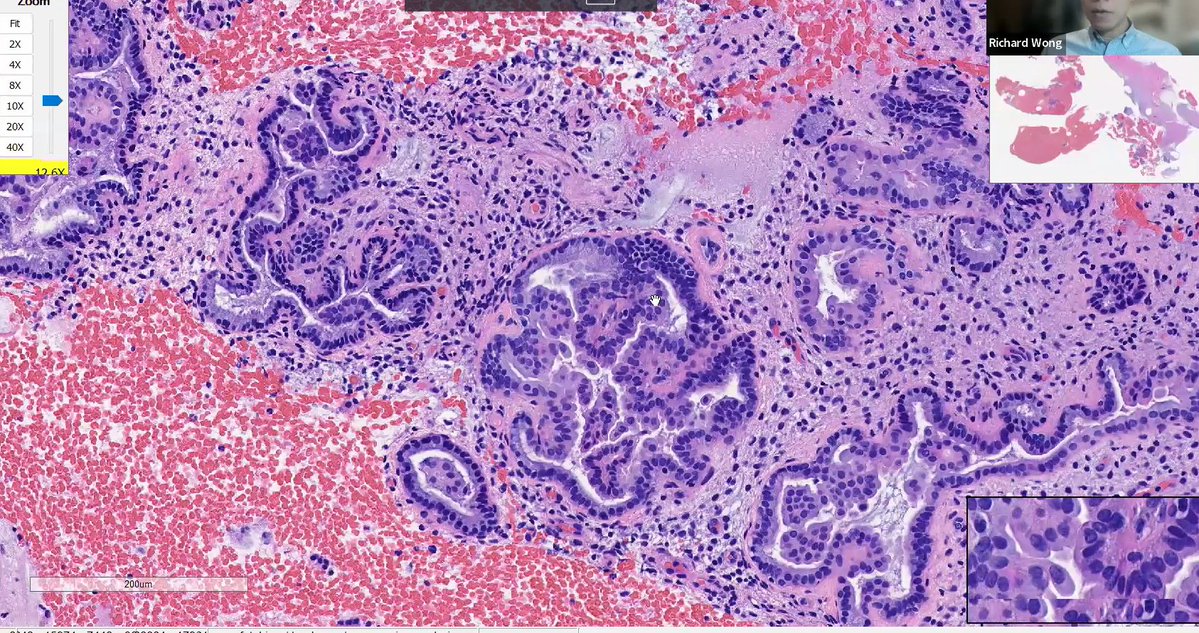

Mucinous lesions of the endometrium Papillary endometrial proliferations with mucinous metaplasia -Mucinous glands with intraglandular simple papillary structures How would you sign out this endometrial biopsy? See next post 👇 Dr. Wong #isgyp #PathTwitter #PathX #pathresidents

Papillary endometrial proliferations with mucinous metaplasia

-Mucinous glands with intraglandular simple papillary structures

How would you sign out this endometrial biopsy?